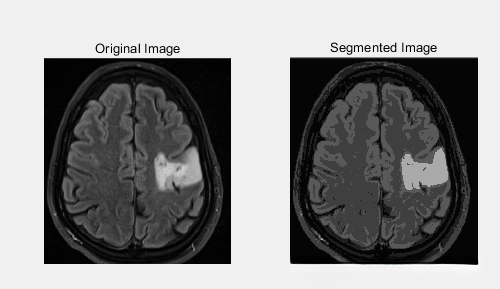

% 显示原始图像和分割结果

subplot(1, 2, 1);

imshow(image);

title('Original Image');

subplot(1, 2, 2);

imshow(uint8(segmented_image));

title('Segmented Image');

图2 实验测试图